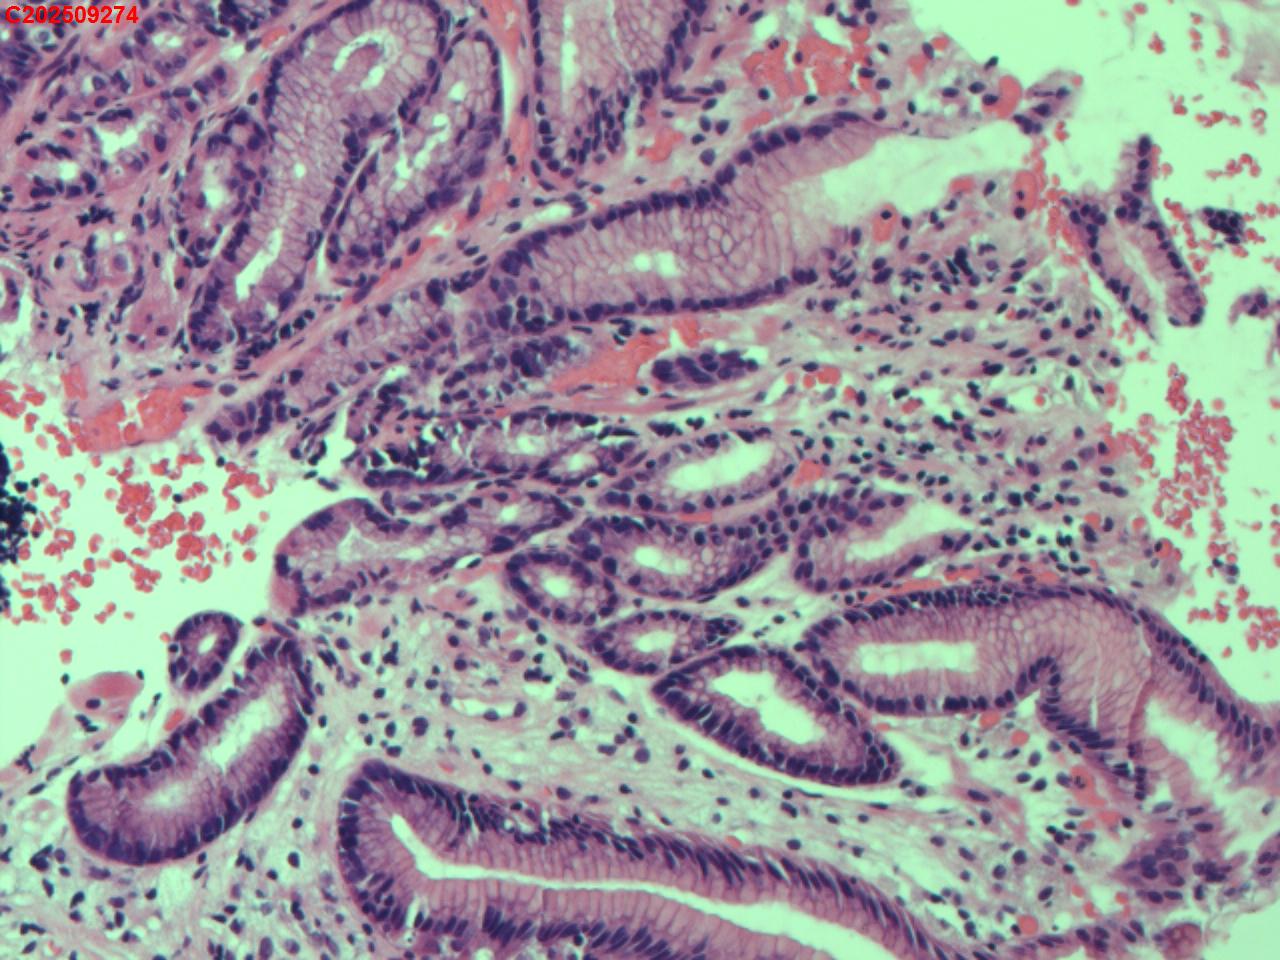

胃窦粘膜

性别

女

年龄

60岁

临床诊断

胃黄斑瘤

一般病史

体检

标本名称

大体所见

胃窦大弯偏前壁可见一扁平状淡黄色粘膜隆起。

图2

送检粘膜呈轻度慢性炎伴表浅糜烂伴胃黄斑瘤形成